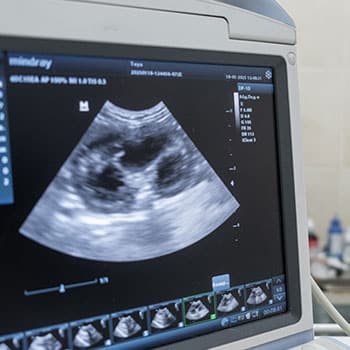

Ultrasound

Ultrasound is a non-invasive imaging technique that provides detailed, three-dimensional, real-time images of your pet’s internal organs without radiation. At Red Pine Trails Animal Hospital, we use ultrasound to evaluate abdominal organs, obtain biopsies, and collect urine. Our hospital also offers echocardiography, a specialized ultrasound examination to assess heart function, through traveling cardiology/imaging specialists.

Abdominal ultrasound

An abdominal ultrasound is a complete scan of your pet’s internal organs, including the liver, kidneys, spleen, bladder, adrenal glands, pancreas, gallbladder, and intestines. Non-invasive abdominal ultrasound is essential for diagnosing tumors, evaluating organ size and appearance, and obtaining ultrasound-guided needle biopsy samples. Our skilled veterinarians obtain detailed measurements and image snapshots during an abdominal scan. These are sent to a radiologist who will then create a report to guide us in developing a treatment plan for your furry pal’s health concerns.